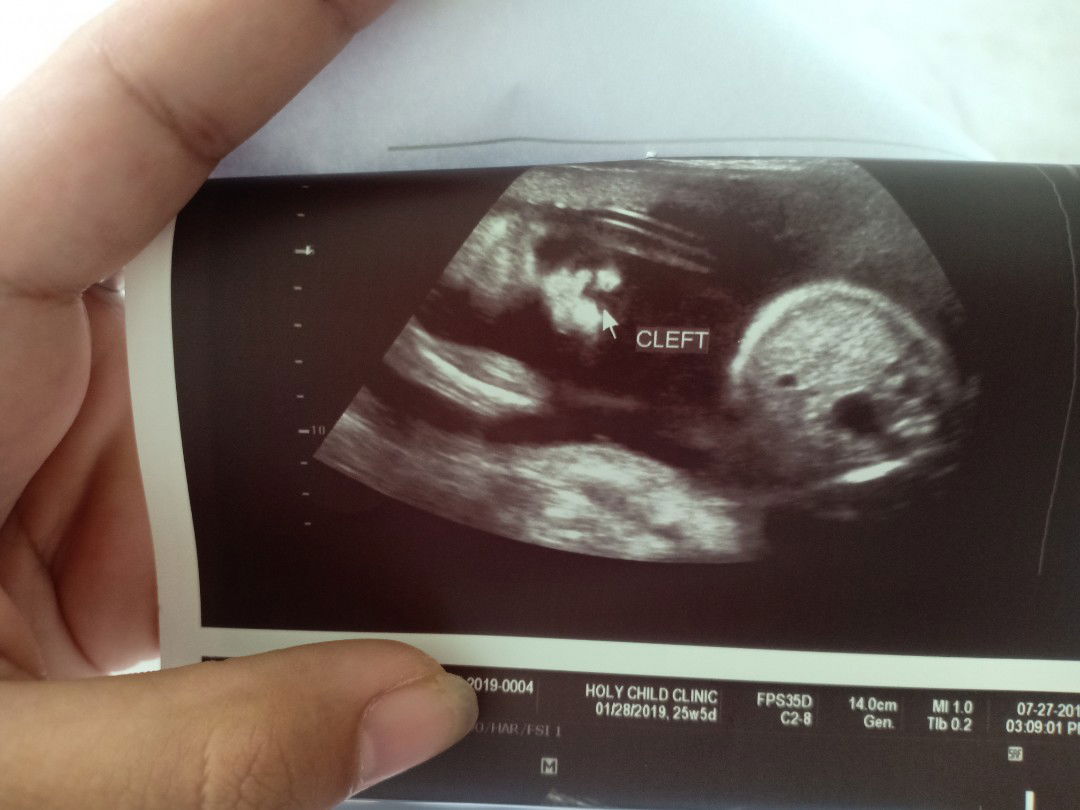

Ultrasound

Hi mamsh, ask ko lang po may chance kayang magkamali yung ultrasound? Based on ultrasound po kasi cleft lip yung baby ko pero wala po sa lahi namin yun. Pwede po kayang mali yun?

Hindi lang po sa lahi nakukuha ang cleft. Minsan po, environment. Nadudulas o nadidisgrasya.